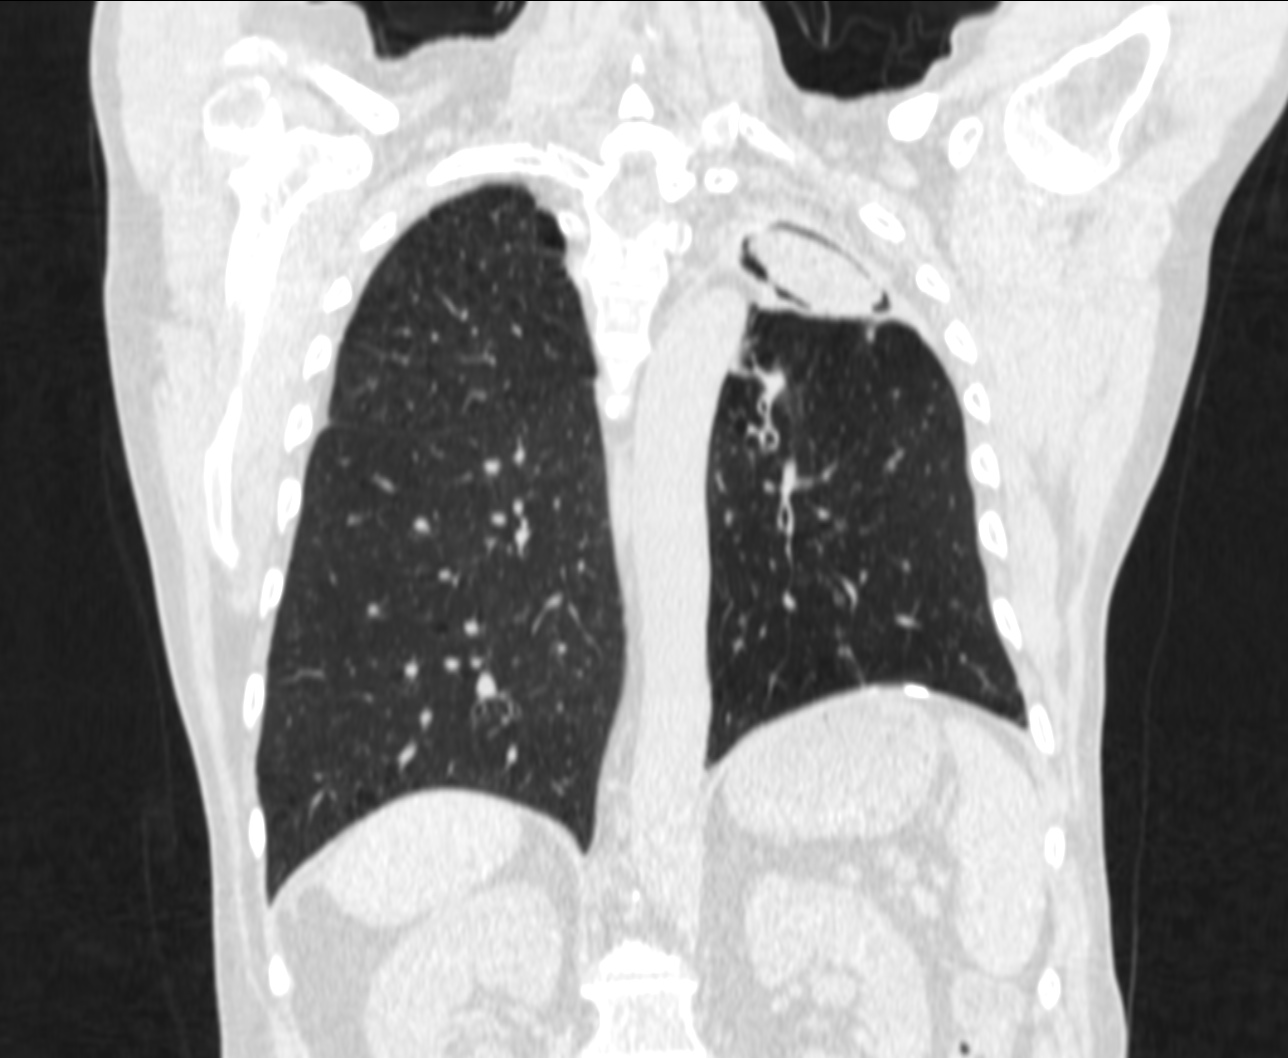

Paciente de 69 años al que se le realiza un estudio programado de TAC por presentar hemoptisis ocasionales. No refiere alteración del estado general, no sd constitucional, IMC 26. En la placa de tórax se observó una masa en LSI.

Veamos los hallazgos de TC.

Por tanto, estamos ante un colapso crónico del LSI con lesión cavitada ocupada en su interior por una imagen redondeada compatible con Aspergiloma que podría ser el responsable de las hemoptisis ocasionales que presenta el paciente.

Presentada arriba. Subtipo caracterizado por la no ivasión de tejidos. Se caracteriza por conglomerados de hifas entrelazadas + mucus + detritus celulares, que se acumulan en una cavidad o bronquio. Se dan en áreas del pulmón con enfermedad o cicatrización previas, siendo la mayor parte de las etiologías subyacente la tuberculosis, la sarcoidosis o absceso. Suelen ser asintomáticos o dar hemoptisis.

Hallazgos radiológicos: Radiografía, masa sólida con densidad de partes blandas dentro de una cavidad. La masa está separada de la pared por aire «Air crescent sign». El aspergiloma se mueve cuando el paciente cambia de posición. (Diagnóstico diferencial: Aspergillus angioinvasiva, Equinococcus, Carinii, TBC, carcinoma, absceso, aneurismas de Rasmussen en TBC.)